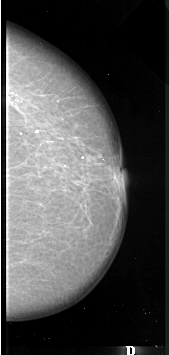

A_1088_1.LEFT_MLO

LEFT_MLO LINES 6451 PIXELS_PER_LINE 2686 BITS_PER_PIXEL 16 RESOLUTION 42 OVERLAY

FILE: A_1088_1.LEFT_MLO.OVERLAY

TOTAL_ABNORMALITIES 1

ABNORMALITY 1

LESION_TYPE CALCIFICATION TYPE PLEOMORPHIC DISTRIBUTION SEGMENTAL

ASSESSMENT 4

SUBTLETY 3

PATHOLOGY MALIGNANT

TOTAL_OUTLINES 1

BOUNDARY